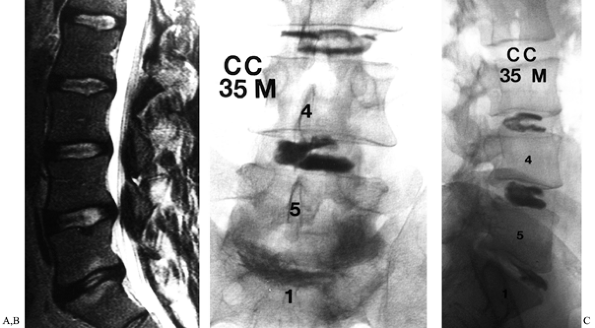

exception, the most helpful diagnostic tool for imaging the lumbar

spine that has previously undergone surgery. The most noteworthy use of

MRI has been in the diagnosis of recurrent disc herniation, using

images obtained before and after the injection of intravenous

paramagnetic contrast material (Gadolinium-DTPA). MRI has 100%

sensitivity, 71% specificity, and 89% accuracy (19).

A nonenhancing soft-tissue mass causing nerve root compression is

strongly suggestive of recurrent disc herniation, whereas Gd-DTPA

enhancement suggests the presence of scar tissue (Fig. 149.3).

![]() |

Figure 149.3.

A 37-year-old woman with a history of three previous discectomies who had recurrent, severe right leg pain, numbness, and a positive straight-leg raising sign. (A) The sagittal MRI demonstrates an apparent disc herniation at L4–L5; (B) the axial T2 image, without contrast, through the L4–L5 disc space demonstrates a soft-tissue mass consistent with disc herniation; (C) the T1 image, following contrast administration. The absence of contrast-enhancement of the mass (white arrow) is diagnostic of recurrent disc herniation, rather than epidural fibrosis; (D) a solid fusion 2 years following repeat discectomy and fusion; the patient continued to have significant back pain. |